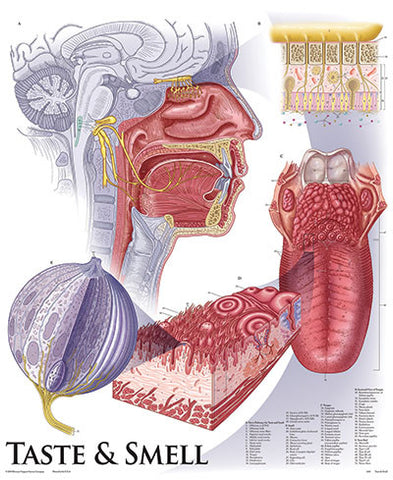

Anatomy

Anatomical models and charts by Body System or Anatomical Region for Nursing, Physical Therapy, and Medical Education.